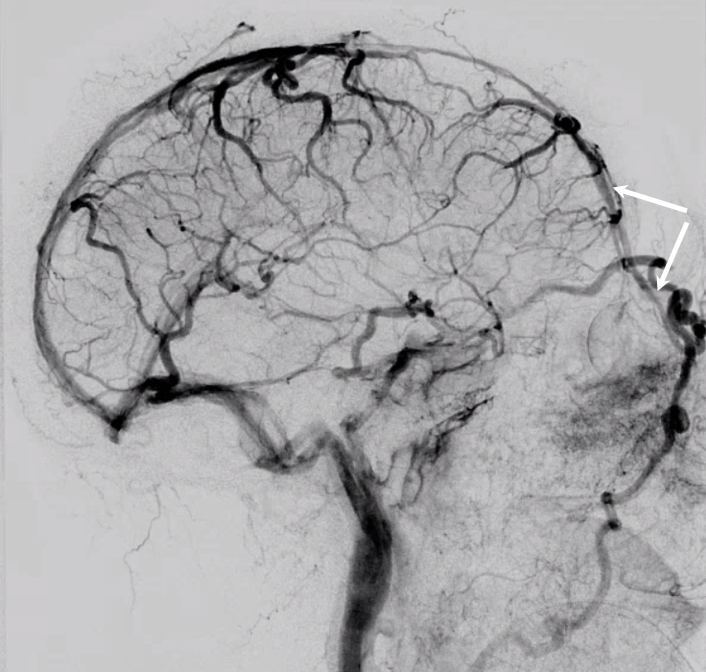

The general neurosurgical fact that the anterior third of the superior sagittal sinus can be safely sacrificed is true almost all the time. When it is not, consequences can be catastrophic. Normally, few veins drain into the anterior 3rd of the SSS, and these usually have collaterals. However, occasionally a large frontal or sylvian vein happens to drain anteriorly. Taking this sinus means risking a venous infarct. Here is an extreme example of dominant inferior left frontal vein draining into the anterior third of the frontal sinus, on MRI. Case courtesy Dr. Howard Riina

Angio is much easier to appreciate. It is well to learn how to spot these veins on MR or CT, as most patients don’t get presurgical angiography for nonvascular lesion

Anaglyph stereo